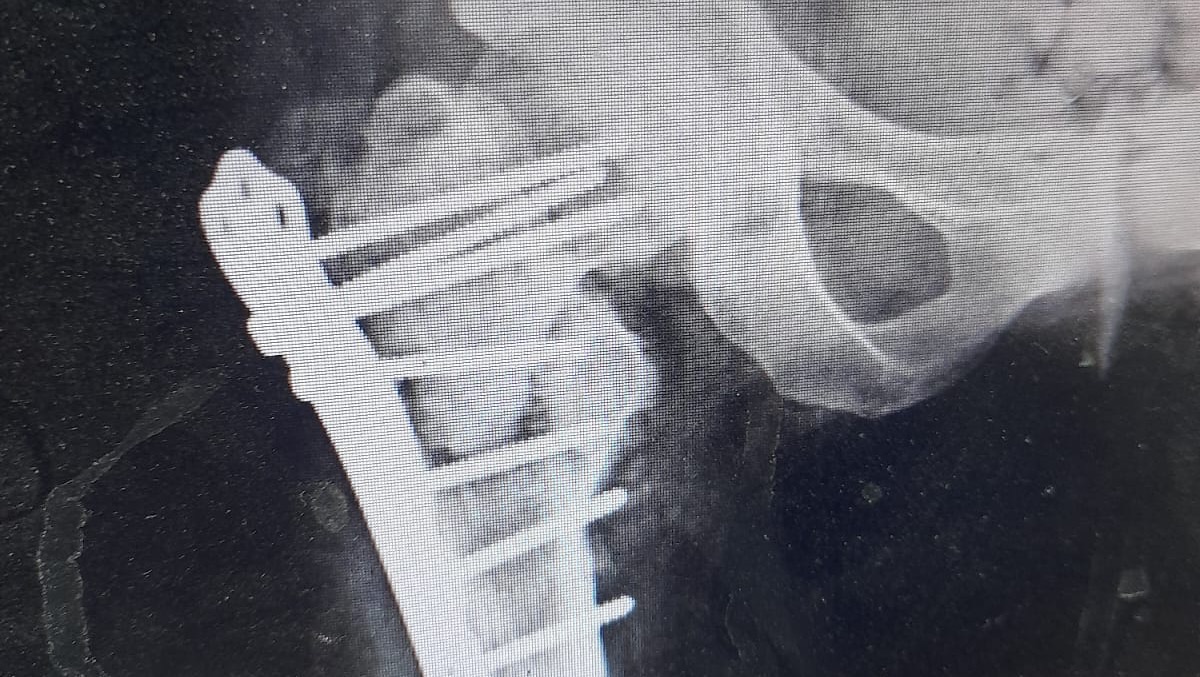

Hello, my name is Johnnie Johnson and I making this go fund me to help my friend Ibrahim Hamdan in Palestine. He is currently injured because of the bombardment and needs $5000 for treatment for his feet. If you can share this around, we will be forever be indebted to you.

If our goals are met all of it will be going directly to Ibrahim to get treatment for his feet.

The cost breakdown consists of $5000 for Ibrahim's treatment, him and his wife's travel cost and $100000 for the rebuild their home. The last $5000 is to cover any fees that might arise.